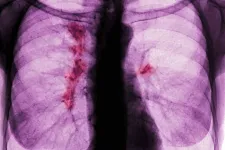

A tüdőrák egy aljas, sunyi betegség, és nincs rá állami szűrőprogramunk sem

Bár a statisztikák szerint javul a halálozási tendencia, egyre több soha nem dohányzó fiatalt is érint a betegség. Ha időben felismerik, az életet menthet.